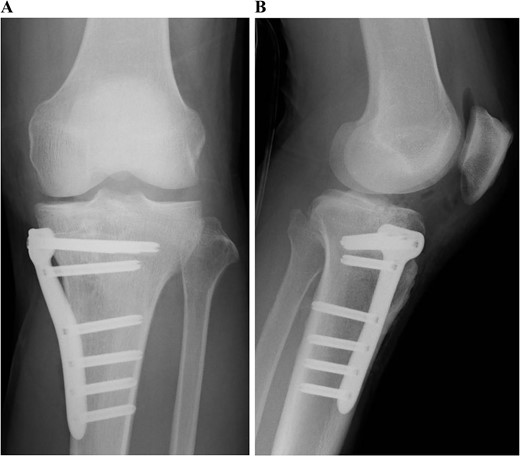

Postoperative plain radiographs of the left knee. Internal fixation was performed with the TriS Medial HTO Plate System.

Postoperative MRI at 1 year after the surgery showed that the transplanted cultured cartilage had successfully integrated without any delamination (Fig. 6). A second-look arthroscopy was performed to evaluate the condition of the transplanted cartilage while removing the plate. The cartilage defect of the medial femoral condyle was covered by hyaline cartilage-like tissue. The depressed articular surface of the medial tibia plateau was smooth without stepping off (Fig. 7). One year after the surgery, the patient resumed daily life and sports activities without any complaint. The patient’s range of motion of the knee was full, and Lysholm’s knee score was 95.